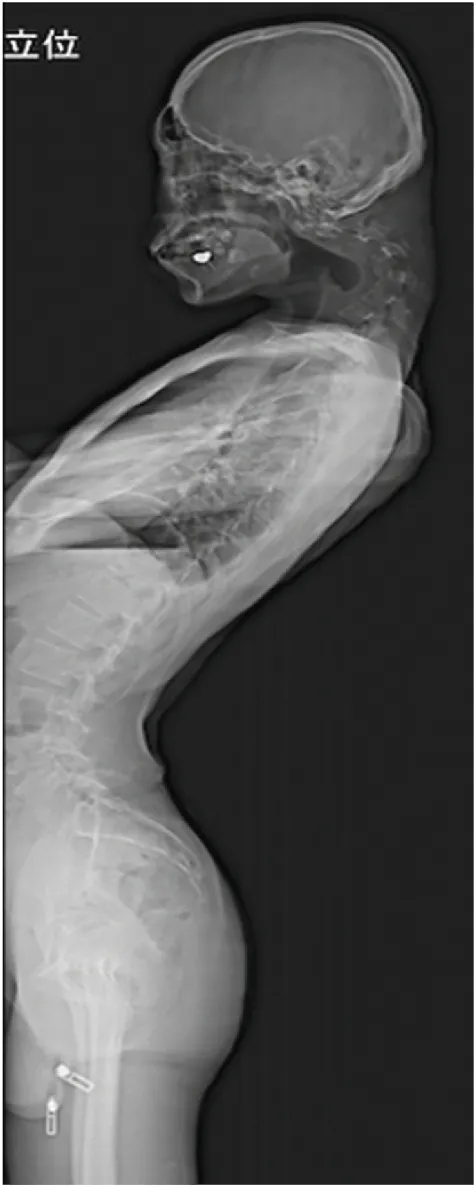

거의 ‘ㄱ’자 형태로 심하게 꺾인 목, 뿔처럼 튀어나온 목뼈.

일본 규슈 오이타현의 오이타 정형외과를 찾은 남성 환자(당시 25세)는 한눈에 봐도 그 상태가 심각했다.

환자는 병원을 찾기 전 6개월 동안 심한 목 통증을 겪고 있었으며 고개를 들어 올릴 수 없다고 호소했다. 목이 너무 심하게 꺾여 그의 턱은 가슴에 거의 맞닿아 있었다.

음식을 씹고 삼키기도 어려워 하루에 겨우 한 끼만 먹을 정도로 식사량이 줄어 있었고, 그 결과 걱정스러울 만큼 체중도 감소한 상황이었다.

또 척수 신경 압박으로 양쪽 팔다리에 저림 증상이 나타났고, 특히 왼손의 힘이 약해지는 척수증도 동반됐다.

이 환자의 심각한 경추 후만증과 ‘머리떨굼증후군’의 직접적인 원인은 좋지 않은 자세로 스마트폰을 과다 사용했기 때문으로 진단됐다. 목을 깊이 구부리고 스마트폰을 내려다보는 습관이 오랜 기간 지속되면서 척추에 악영향을 끼쳤다는 것이다.

정밀검사를 진행한 결과 목뼈가 왜곡되고 탈구됐으며, 시간이 지나면서 척추(특히 경막) 부위에 흉터 같은 조직이 증식한 것이 관찰됐다.